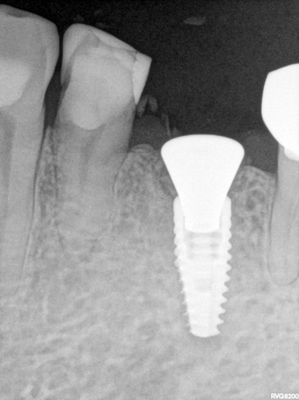

atraumatic exo, buccal bone intact, implant placed slightly distal and palatal to socket, socket grafted with allograft, healing abutment placed, no sutures